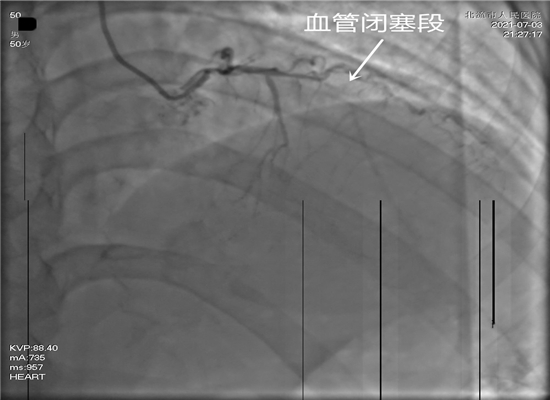

病人转送至导管室,准备手术

时间就是生命,这是一场与死神生死竞速的硬仗。21时15分,病人进入导管室,在赵子粼博士的主持下,张轩副主任亲自操刀,介入团队密切配合,快速穿刺桡动脉、置管、造影,升压,开通闭塞血管,植入支架。经过约50分钟的全力救治,成功挽救了患者的生命。目前,术后患者症状明显改善,恢复较好。